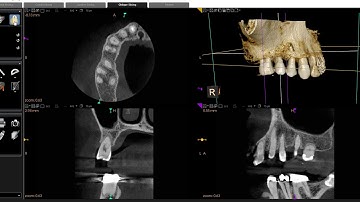

Using Deep Learning from CBCT Scans (Visualization)